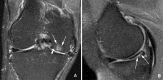

Main outcome measures: Prevalence of MRI findings that are suggestive of knee osteoarthritis (osteophytes, cartilage damage, bone marrow lesions, subchondral cysts, meniscal lesions, synovitis, attrition, and ligamentous lesions) in all participants and after stratification by age, sex, body mass index (BMI), and the presence or absence of knee pain. Pain was assessed by three different questions and also by WOMAC questionnaire.

Results: Of the 710 participants, 393 (55%) were women, 660 (93%) were white, and 206 (29%) had knee pain in the past month. The mean age was 62.3 years and mean BMI was 27.9. Prevalence of "any abnormality" was 89% (631/710) overall. Osteophytes were the most common abnormality among all participants (74%, 524/710), followed by cartilage damage (69%, 492/710) and bone marrow lesions (52%, 371/710). The higher the age, the higher the prevalence of all types of abnormalities detectable by MRI. There were no significant differences in the prevalence of any of the features between BMI groups. The prevalence of at least one type of pathology ("any abnormality") was high in both painful (90-97%, depending on pain definition) and painless (86-88%) knees.

Conclusions: MRI shows lesions in the tibiofemoral joint in most middle aged and elderly people in whom knee radiographs do not show any features of osteoarthritis, regardless of pain.